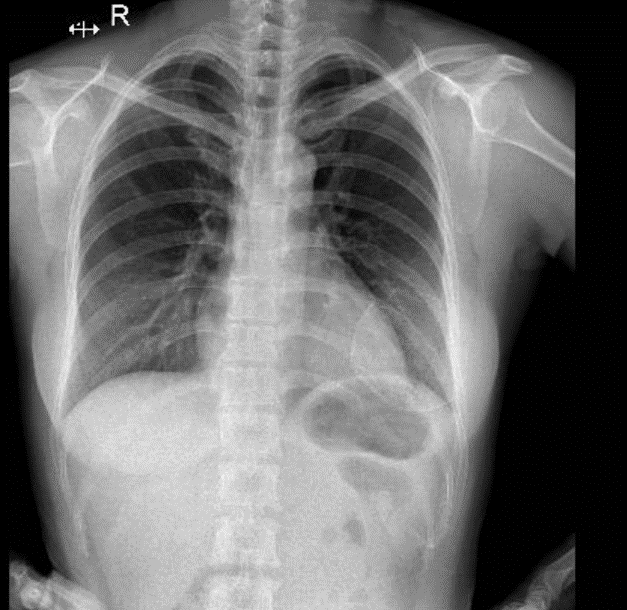

Hãy phân tích tình huống NỮ 40 tuổi -CĐ: Thẩm mỹ

1-Ảnh giả thành ngực hai bên